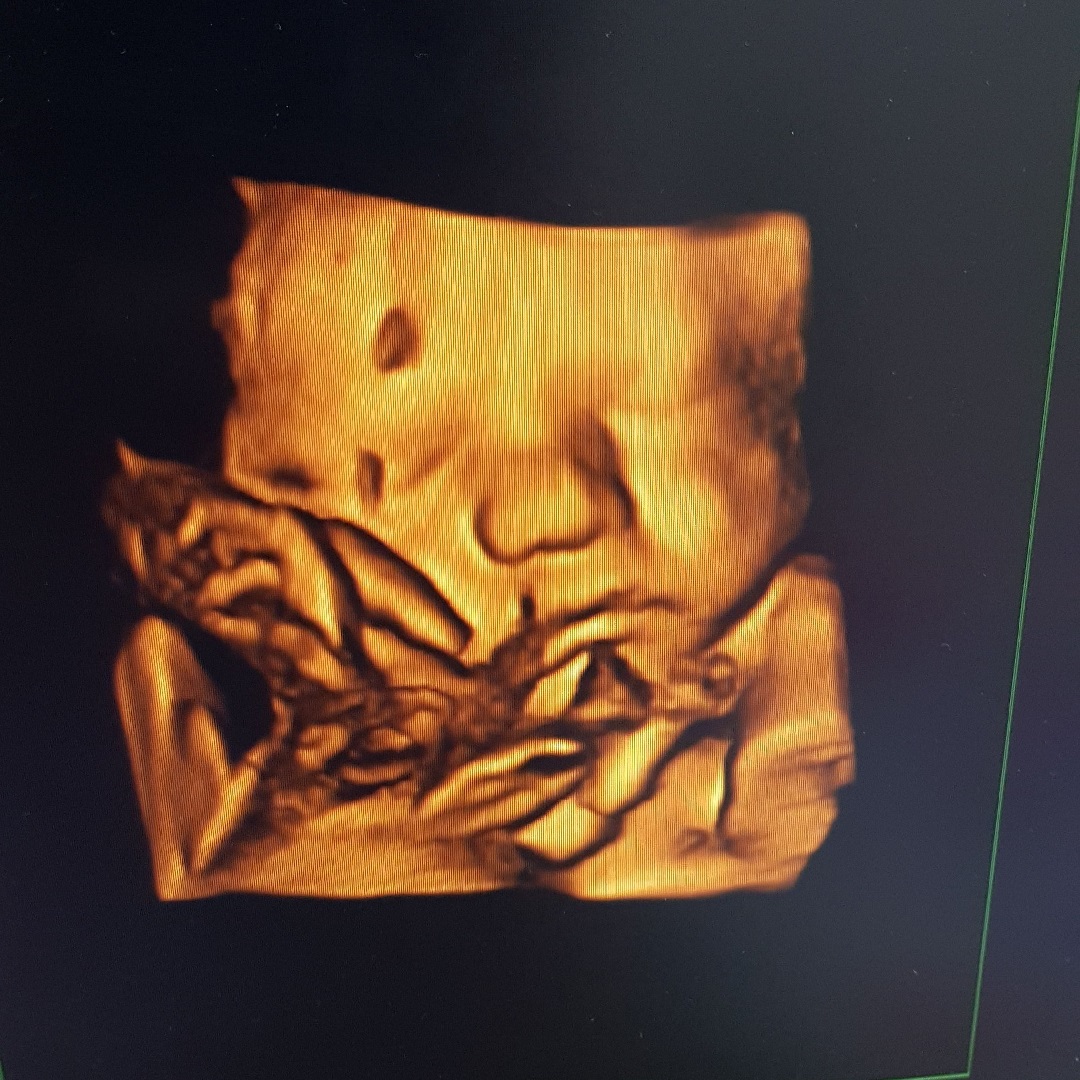

If you’re an expectant mommy, a 3D or 4D Scan can be a touching experience. Contact the helpful sisters at Homegrown Babies at Mopani Crossing Centre on 013 755 5500 for more information.